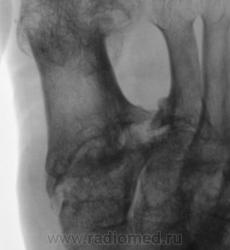

Пациентка направлена на рентгенографию стоп в прямой проекции с диагнохом - "Поперечное плоскостопие".

Произведена рентгенография обеих стоп в прямой проекции.

Сильно сомневаюсь в болезни Олье - затронуты только суставные концы, диафизы интактны. Считаю - остеоартропатия, вероятнее всего - подагра

Классика подагры - наличие тофусов в параартикулярных мягких тканях... Механизм поражения скелета при подагре - атрофия от давления тофусами. А здесь - их совершенно не видно, мягкие ткани просто отодвинуты, но обьем то их - нормальный...